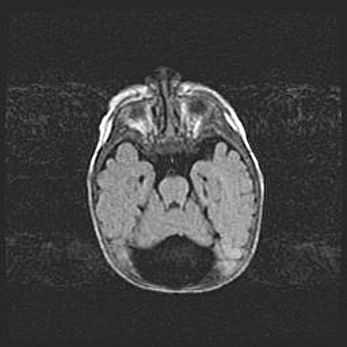

Наружная гидроцефалия с возможной атрофией височных областей.

Возраст: 28 дней

Вес: 3670 г

Пол: мужской

Окружность головы: 38 см

Срок гестации: 40 недель

Гидроцефалия головного мозга у новорожденных – это заболевание, которое характеризуется скоплением избыточного количества спинномозговой жидкости в желудочковой системе головного мозга в результате затруднения её перемещения от места выработки к месту поглощения в кровеносную систему или вследствие нарушения абсорбции. При открытой наружной форме гидроцефалии у новорожденных расширяются и переполняются субарахноидные пространства.

При нормотензивных  формах,  которые,  как  правило,  являются  следствием  перенесенных ишемических  повреждений  паренхимы  мозга,  возможно  сочетание микроцефалии  с нормотензивной гидроцефалией. В основе данных изменений лежит атрофия больших полушарий с преимущественной  локализацией  в  лобно-височных  областях.